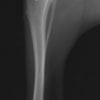

術前左後肢側面像

術後左後肢側面像

本症例は、走った後に左後肢を挙上していることを主訴に来院されました。触診時に左膝関節のクリック音を聴取、レントゲン検査にて左脛骨の前方変位が認められました。術中に、前十字靱帯の断裂及び内側半月板の損傷、内側の軟部組織の顕著な腫脹を確認。半月板切除、TPLOを実施しました。周囲組織への炎症の波及もあったため回復に時間を要しておりますが、徐々に跛行頻度は減少傾向にあり、現在も経過観察中です。術前に約29°あったTPAは術後に約10°まで矯正されました。

手術前後のTPA(脛骨高平部の角度)を測定しています。

約29°から約10°へ矯正されています。